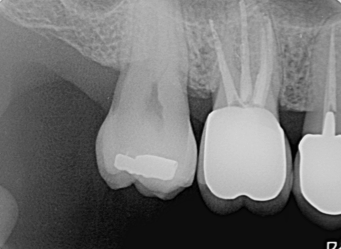

多根根管治療

治療後